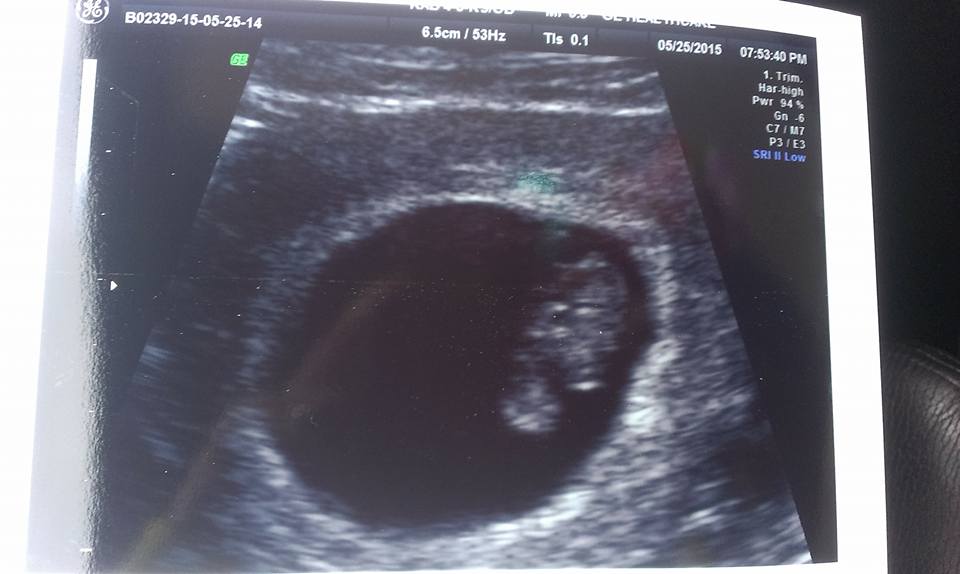

6weeks, 10weeks and 12 week ultrasound :)